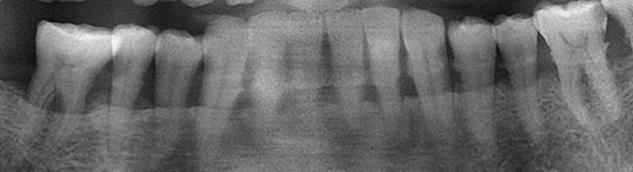

第三位还是比较不错朋友的亲戚,过来洗牙,一看这不是洗牙能解决的问题,有些牙都留不了了,拍了片子更直接清楚,包着牙根的骨头,都被牙结石顶的吸收2/3了,洗完后牙齿肯定会松的更厉害,有的牙齿,表面看着好好地,一点 坏都没有,只能拔除了,情况都告知后朋友亲戚接受不了,但那又怎么样,我得说清楚,做不做还得患者自己做决定,大家看看下面这图片吧